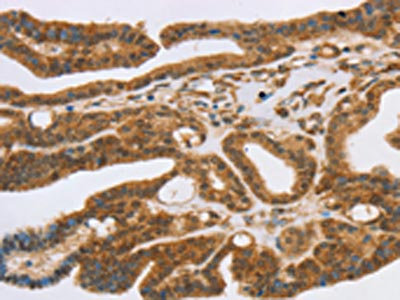

The image on the left is immunohistochemistry of paraffin-embedded Human liver cancer tissue using CSB-PA146812(SLC7A9 Antibody) at dilution 1/35, on the right is treated with synthetic peptide. (Original magnification: ×200)

The image on the left is immunohistochemistry of paraffin-embedded Human thyroid cancer tissue using CSB-PA146812(SLC7A9 Antibody) at dilution 1/35, on the right is treated with synthetic peptide. (Original magnification: ×200)